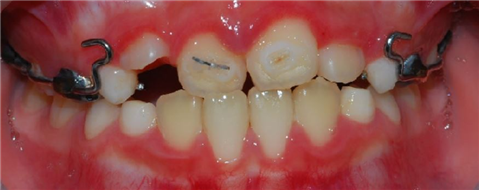

| 치료중: 반대교합이 심할 때는 윗니에 교정장치를 걸어서 앞으로 끌어내면 반대교합을 교정할 수 있다. 윗턱에 상악골을 견인하는 장치가 보인다. |